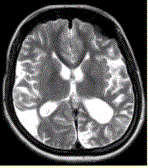

问题 女性,22岁。癫痫发作及智力异常。MRI显示见下图。 关于该病描述正确的是

选项 A.脑萎缩 B.双侧顶枕叶软化灶 C.蛛网膜囊肿 D.双侧顶枕叶脑梗死 E.脑积水 F.脑炎

答案 AB

解析 AB